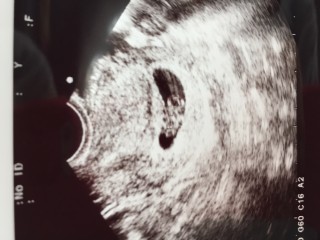

最初の検診から、2週間後に行った時の写真です。ちゃんと育ってるか、すごく不安でした。0.8㎝から1.6㎝に元気に育ってました。 でも、子宮に6㎝の腫瘍が見つかり、ものすごい不安と戦ってます。 無事に子供が生まれてくることを祈るしかないんですけどね。